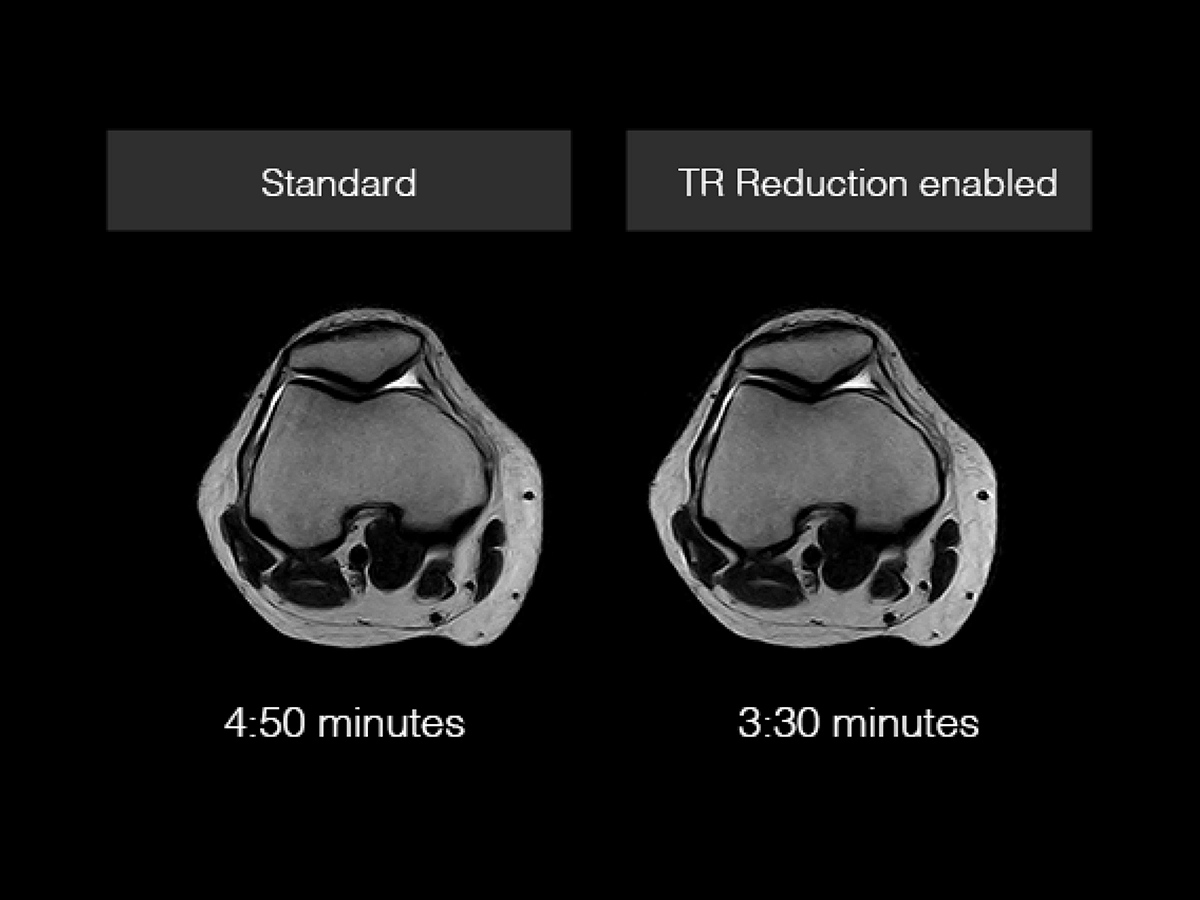

TR Reduction

TR reduction is an Esaote patented acquisition methods based on FSE sequences. TR reduction technology manages the Echo Train Length with a tailored algorithm for data acquisition and reconstruction of the K Space resulting in:

- Reduction of scan time up to 30% (depending on TE, ETL and ESP).

- Reduced image blurring due the shorter Echo Train Length.

- Adaptive and intelligent technology to improve the choice of the optimal parameters.

- Compatible with other imaging sequences like SpeedUp and MAR sequence.